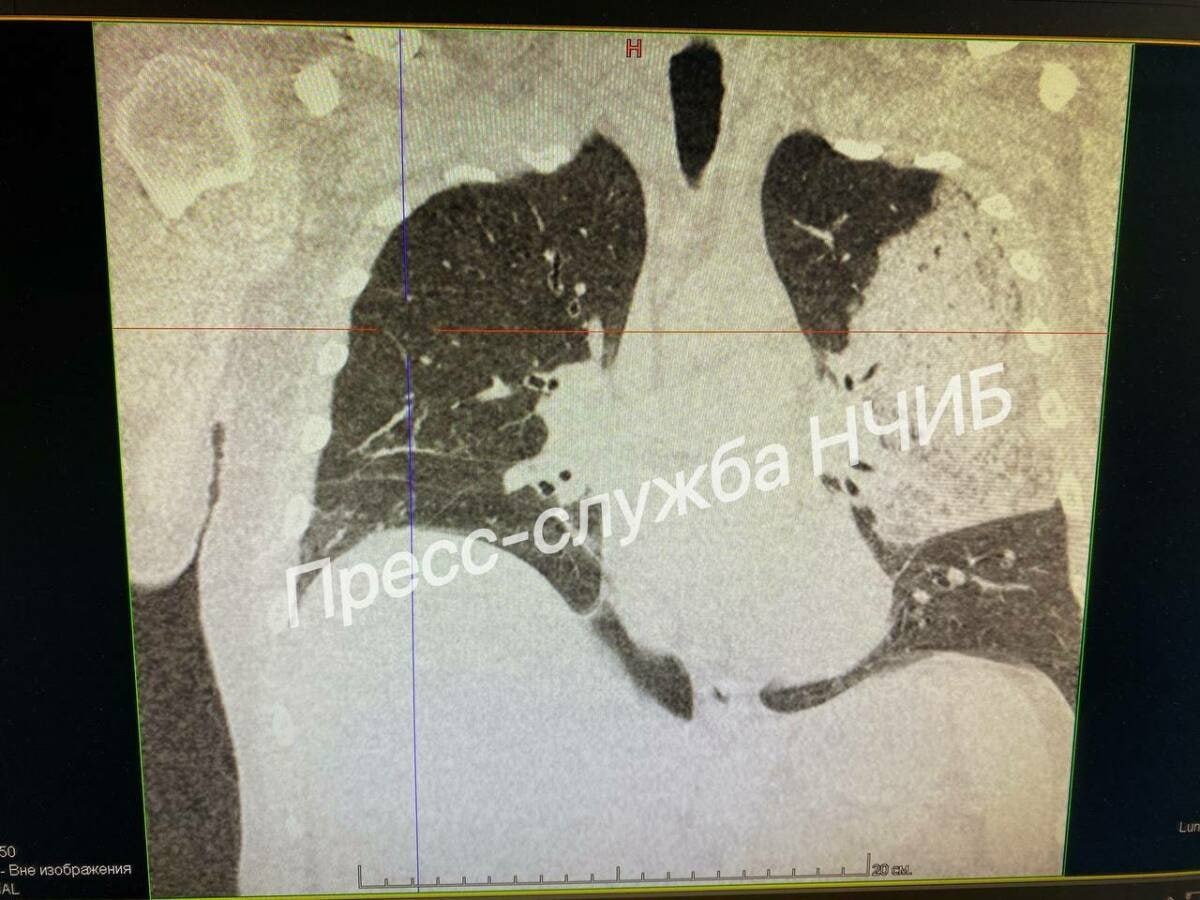

πŸ‘πŸ‘¨β€βš•οΈΠ’Ρ€Π°Ρ‡ΠΈ НабСрСТночСлнинской ΠΈΠ½Ρ„Π΅ΠΊΡ†ΠΈΠΎΠ½Π½ΠΎΠΉ Π±ΠΎΠ»ΡŒΠ½ΠΈΡ†Ρ‹ спасли ΠΌΡƒΠΆΡ‡ΠΈΠ½Ρƒ с тяТСлым ΠΏΠΎΡ€Π°ΠΆΠ΅Π½ΠΈΠ΅ΠΌ Π»Π΅Π³ΠΊΠΈΡ…

Для поддСрТания ΠΆΠΈΠ·Π½Π΅Π½Π½Ρ‹Ρ… Ρ„ΡƒΠ½ΠΊΡ†ΠΈΠΉ Π²Ρ€Π°Ρ‡ΠΈ ΠΏΡ€ΠΈΠΌΠ΅Π½ΠΈΠ»ΠΈ ΠΈΠ½Ρ‚Π΅Π½ΡΠΈΠ²Π½ΡƒΡŽ Ρ‚Π΅Ρ€Π°ΠΏΠΈΡŽ. На восьмой дСнь Π±Ρ‹Π»Π° Π²Ρ‹ΠΏΠΎΠ»Π½Π΅Π½Π° трахСостомия, послС Ρ‡Π΅Π³ΠΎ появились ΠΏΠ΅Ρ€Π²Ρ‹Π΅ ΠΏΡ€ΠΈΠ·Π½Π°ΠΊΠΈ ΡƒΠ»ΡƒΡ‡ΡˆΠ΅Π½ΠΈΡ.

«Он ΠΏΡ€ΠΎΠ²Ρ‘Π» Π½Π° Π˜Π’Π› Π΄Π΅ΡΡΡ‚ΡŒ Π΄Π½Π΅ΠΉ. Π˜Π·Π½Π°Ρ‡Π°Π»ΡŒΠ½ΠΎ ΠΌΡ‹ Π½Π΅ Π΄Π°Π²Π°Π»ΠΈ оптимистичных ΠΏΡ€ΠΎΠ³Π½ΠΎΠ·ΠΎΠ², Π½ΠΎ благодаря ΠΊΠΎΠΌΠ°Π½Π΄Π½ΠΎΠΉ Ρ€Π°Π±ΠΎΡ‚Π΅ ΠΈ Π³Ρ€Π°ΠΌΠΎΡ‚Π½ΠΎΠΌΡƒ Π»Π΅Ρ‡Π΅Π½ΠΈΡŽ ΡƒΠ΄Π°Π»ΠΎΡΡŒ Π΄ΠΎΠ±ΠΈΡ‚ΡŒΡΡ ΠΏΠΎΠ»ΠΎΠΆΠΈΡ‚Π΅Π»ΡŒΠ½ΠΎΠΉ Π΄ΠΈΠ½Π°ΠΌΠΈΠΊΠΈΒ», - ΠΎΡ‚ΠΌΠ΅Ρ‚ΠΈΠ» Π ΠΈΡˆΠ°Ρ‚ Π₯Π°ΠΊΠΈΠΌΠΎΠ².

ΠŸΠΎΡΡ‚Π΅ΠΏΠ΅Π½Π½ΠΎ ΠΏΠ°Ρ†ΠΈΠ΅Π½Ρ‚Π° ΠΎΡ‚ΠΊΠ»ΡŽΡ‡ΠΈΠ»ΠΈ ΠΎΡ‚ Π°ΠΏΠΏΠ°Ρ€Π°Ρ‚Π° искусствСнной вСнтиляции Π»Π΅Π³ΠΊΠΈΡ…, ΠΏΠ΅Ρ€Π΅Π²Π΅Π»ΠΈ Π² ΠΏΠ°Π»Π°Ρ‚Ρƒ, Π° Π·Π°Ρ‚Π΅ΠΌ выписали.